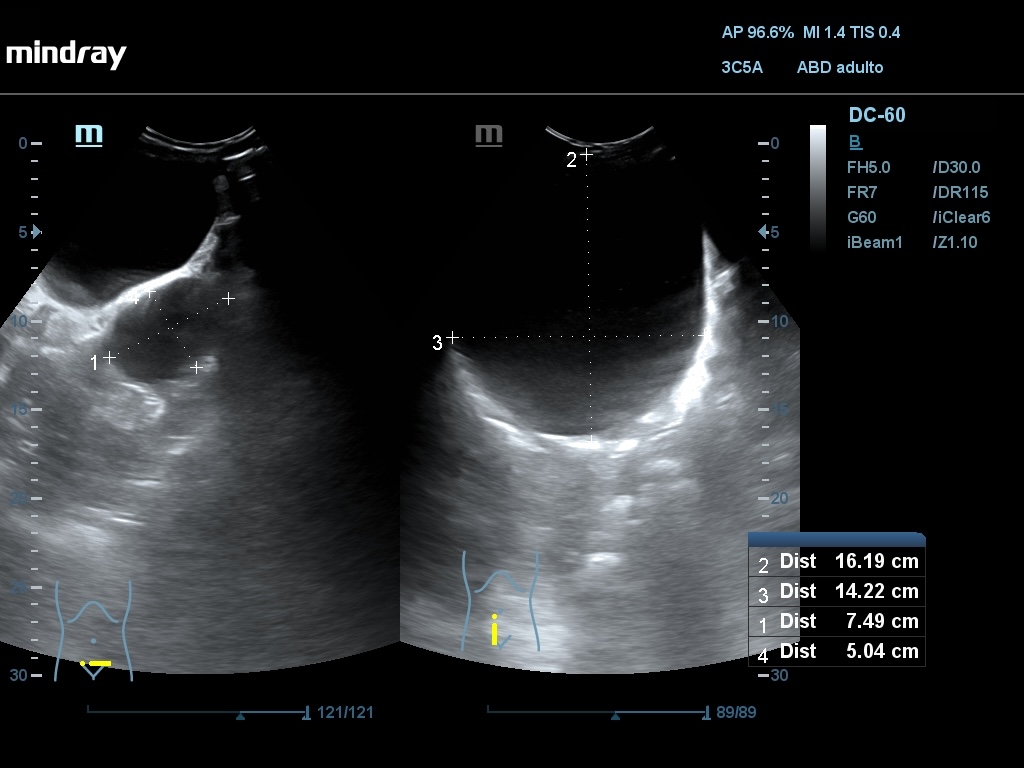

Ecografía abdominal: Se observan varios quistes simples a nivel hepático, siendo el mayor de 52,4 mm, en ambos riñones siendo el mayor de 77 x 83 mm en RD y de 80 x 64 mm en RI. En hipogastrio se observa imagen redondeada, anecogénica, con sombra posterior, de borde liso y fino, no tabicada, de aprox. 161 x 142 mm y otra de características similares de 74 x 54 mm.

Se describe imagen de 22 cm con probable localización anexial izq. El crecimiento del quiste ha condicionado un desplazamiento del mismo hacia cavidad abdominal derecha, desplazando lateralmente las asas del intestino y colon.

Ginecología confirman diagnóstico mediante ecografía vaginal de una formación anecogénica de 170 x 120 mm de localización centropélvica.

La existencia de otros quistes de tamaño considerable en la cavidad abdominal debido a la PQ, puede dificultar la determinación del origen de este en la ecografía abdominal, sobre todo cuando son de tamaño grande.